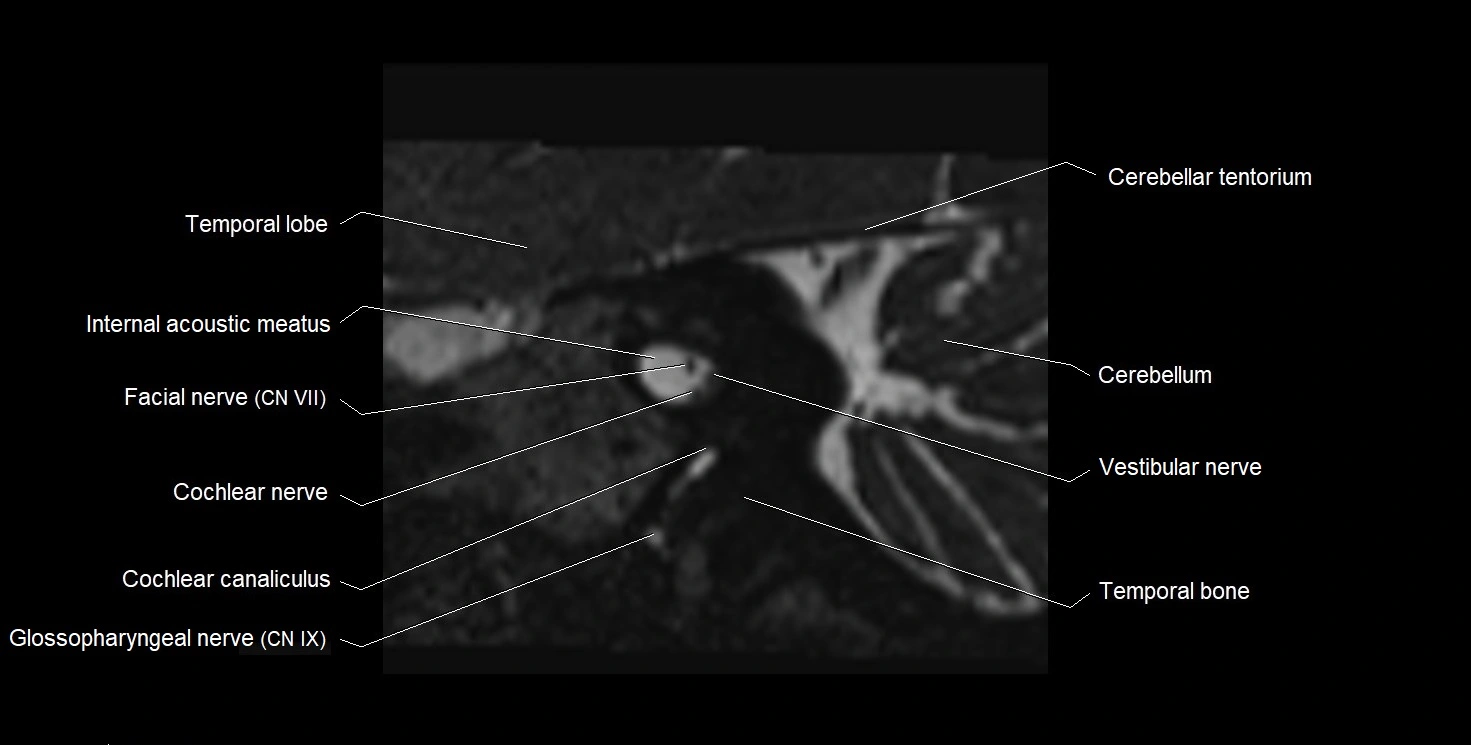

MRI images

image